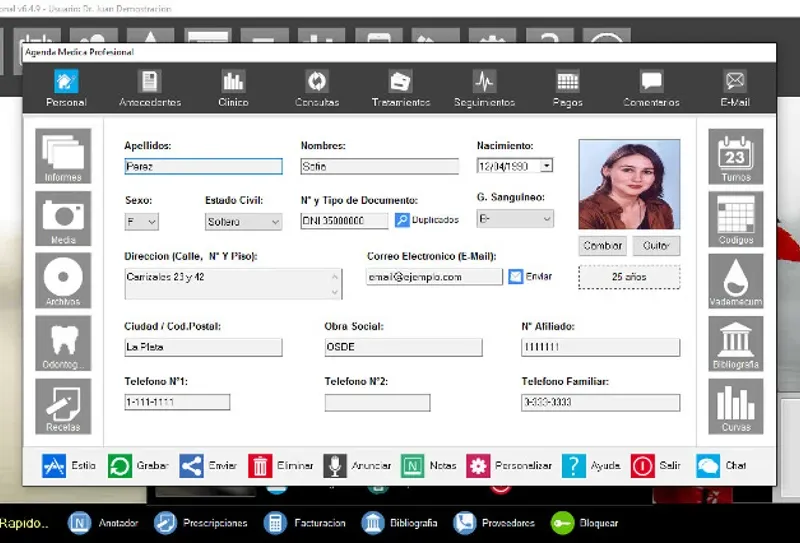

Agenda Medica - это инновационное приложение для управления расписанием медицинского офиса. Оно позволяет легко и эффективно планировать приёмы пациентов, управлять расписанием врачей и оптимизировать рабочий процесс клиники. С Agenda Medica вы сможете сократить время на административные задачи, улучшить качество обслуживания пациентов и повысить общую продуктивность вашего медицинского учреждения. Приложение предлагает интуитивно понятный интерфейс, интеграцию с электронными медицинскими картами и возможность отправки автоматических напоминаний пациентам. Agenda Medica - ваш надежный помощник в организации медицинского офиса.

Agenda Medica - medical office scheduler

Agenda Medica - medical office scheduler скачать бесплатно на ПК и телефон